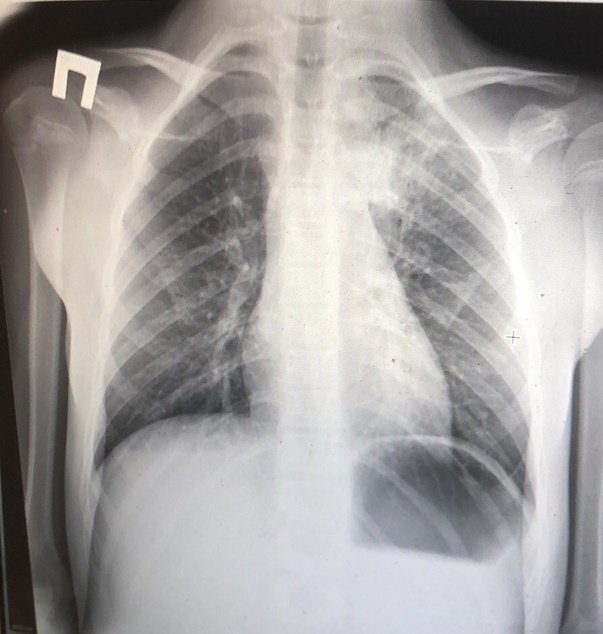

При пневмонии, на рентгеновском снимке легких, видны следующие признаки:

• в разных частях органа находятся очаги затемнения, имеющие неровные контуры и размер 3-12 мм;

• различаются тени по внешнему виду (овальные, кольцевидные, круглые), интенсивности цвета – чем темнее будет пятно, тем сильнее патологический процесс;

• если поражены лимфатические узлы и нарушено кровоснабжение органа, может быть заметно изменение корней лёгких, если поражена плевра – видны нарушения в рисунке куполов диафрагмы.

На рентгеновском снимке пневмония выглядит следующим образом: